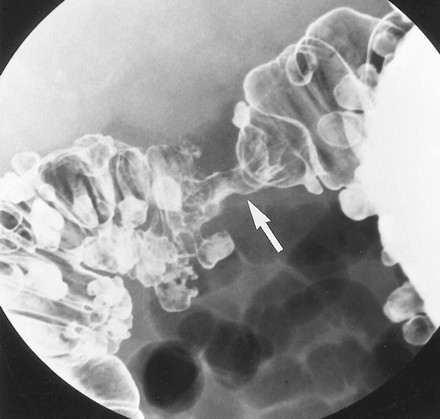

Các u tuyến có sự thay đổi lông nhung mao mức độ cao gọi là u tuyến lông nhung. Chúng là một dạng đặc biệt vì có nguy cơ thoái biến ác tính cao hơn các u tuyến ống hoặc u tuyến ống-lông nhung. Các u tuyến lông nhung có thể nhận ra trên các ảnh cản quang kép dưới hình các tổn thương polyp có bề mặt lưới hoặc nốt do baryt kẹt giữa các lông của khối u (Hình 7) [4].

Các khối u tuyến lông nhung có thể là các tổn thương chia thùy, phẳng, còn gọi là các tổn thương hình “tấm thảm”, chúng được mô tả là các thay đổi tinh vi ở bề mặt đại tràng, lồi rất ít hoặc không lồi vào lòng đại tràng. Kích thước trung bình của u 4 x 6 cm, thường mọc ở trực tràng, manh tràng, và đại tràng lên. Trên phim cản quang kép nhìn thẳng, các nốt to, nhỏ tụ với nhau thành mảng, phân cách nhau bởi các lưới mảnh đọng baryt (Hình 8) [5]. Khi nhìn nghiêng, tổn thương có bờ không đều, trái với bờ nhẵn của niêm mạc bình thường bao quanh.

Hình 7. Hình cản quang kép nằm ngửa cho thấy khối u tuyến lông nhung ở trực tràng. Tổn thương là khối dạng polyp (các mũi tên) với bề mặt nốt và lưới.

Hình 8. Hình cản quang kép chếch sau phải bộc lộ một tổn thương hình thảm. Chú ý bề mặt hình lưới-nốt của tổn thương (mũi tên) ở manh tràng do baryt lấp đầy các kẽ hở của khối u tuyến lông nhung.